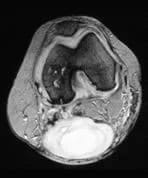

Popliteal Cyst

A patient presents with pain at the back of the knee.

There is a large posterior popliteal fluid collection. Marked tri-compartmental degenerative change in the medial joint compartment is also seen. These latter changes are in keeping with secondary avascular necrosis. Also present is a large joint effusion with marked synovitis and synovial hypertrophy.